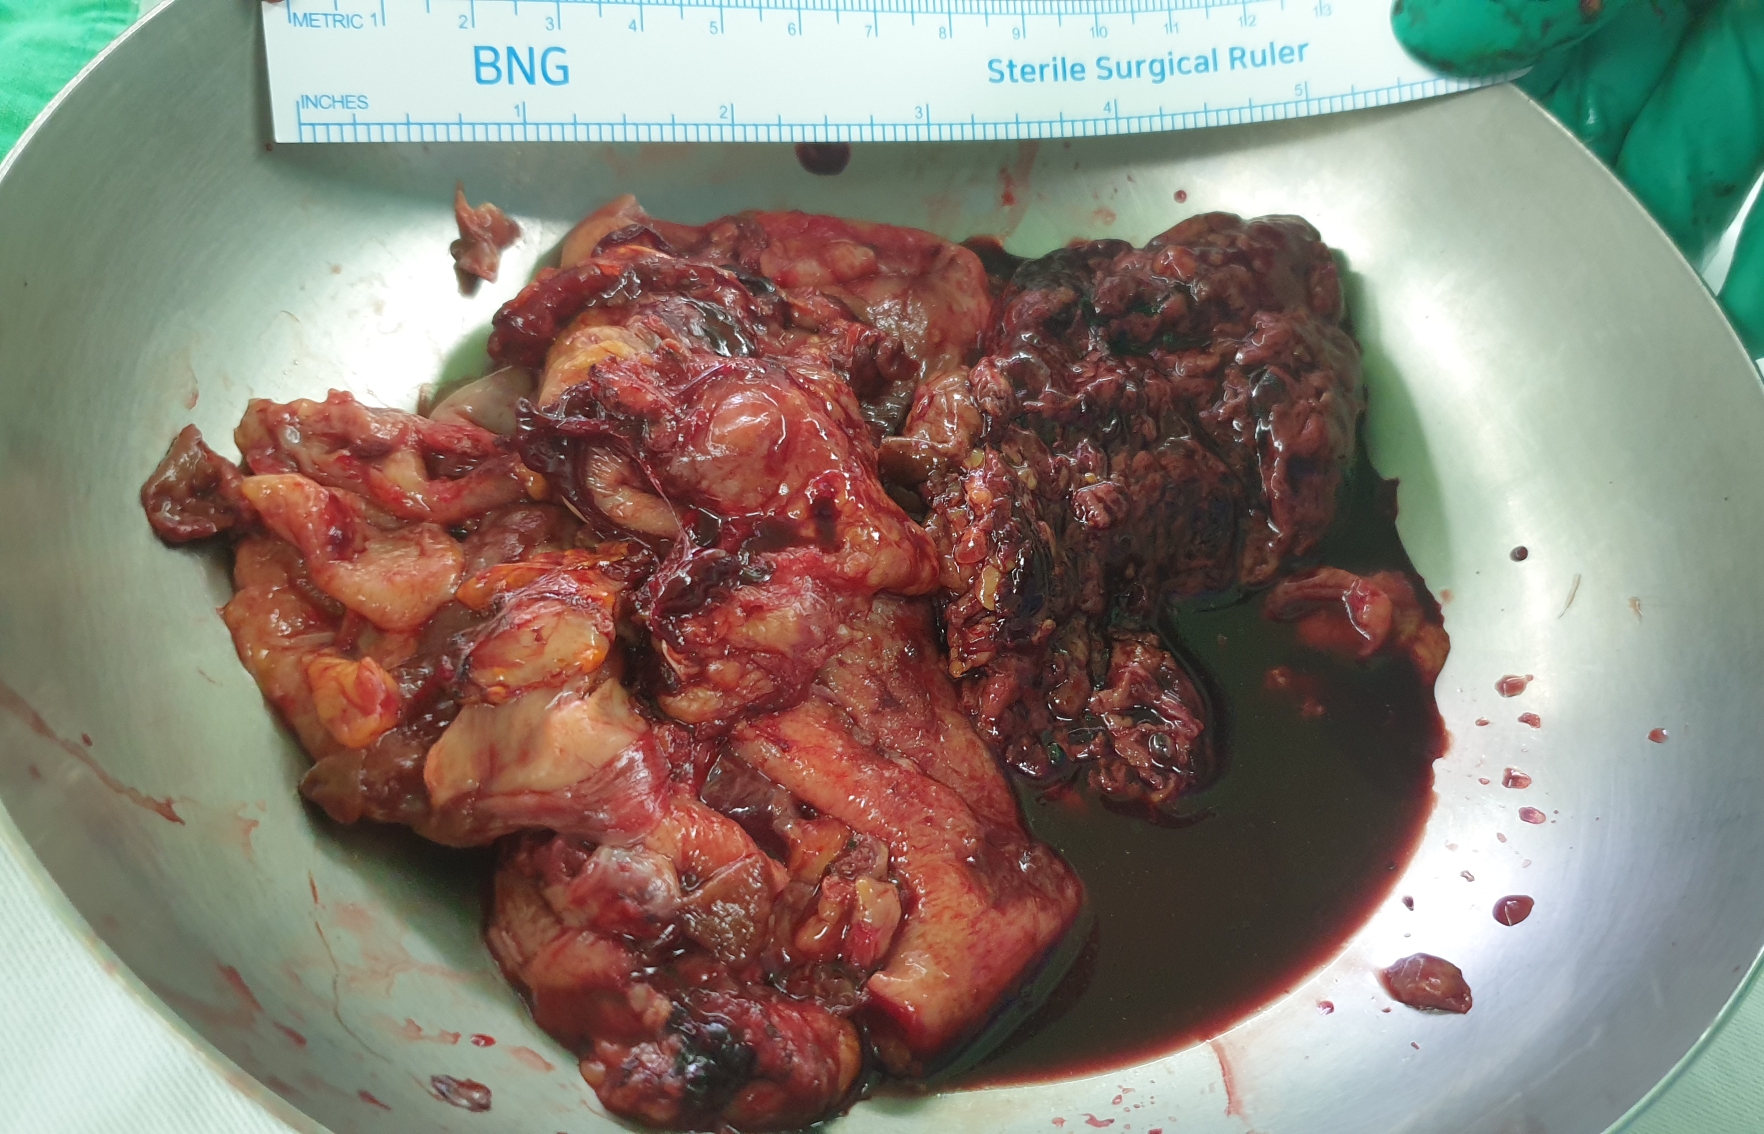

낭종을 제거하고 작은 구멍으로 빼내야 하기 때문에 여러 조각으로 분리되었습니다.

사이즈가 엄청나게 큽니다. 낭종안에 액체가 빠져서 저정도 사이즈로 보이지 만약 액체가 있다면 사이즈는 더 어마어마하겠죠?